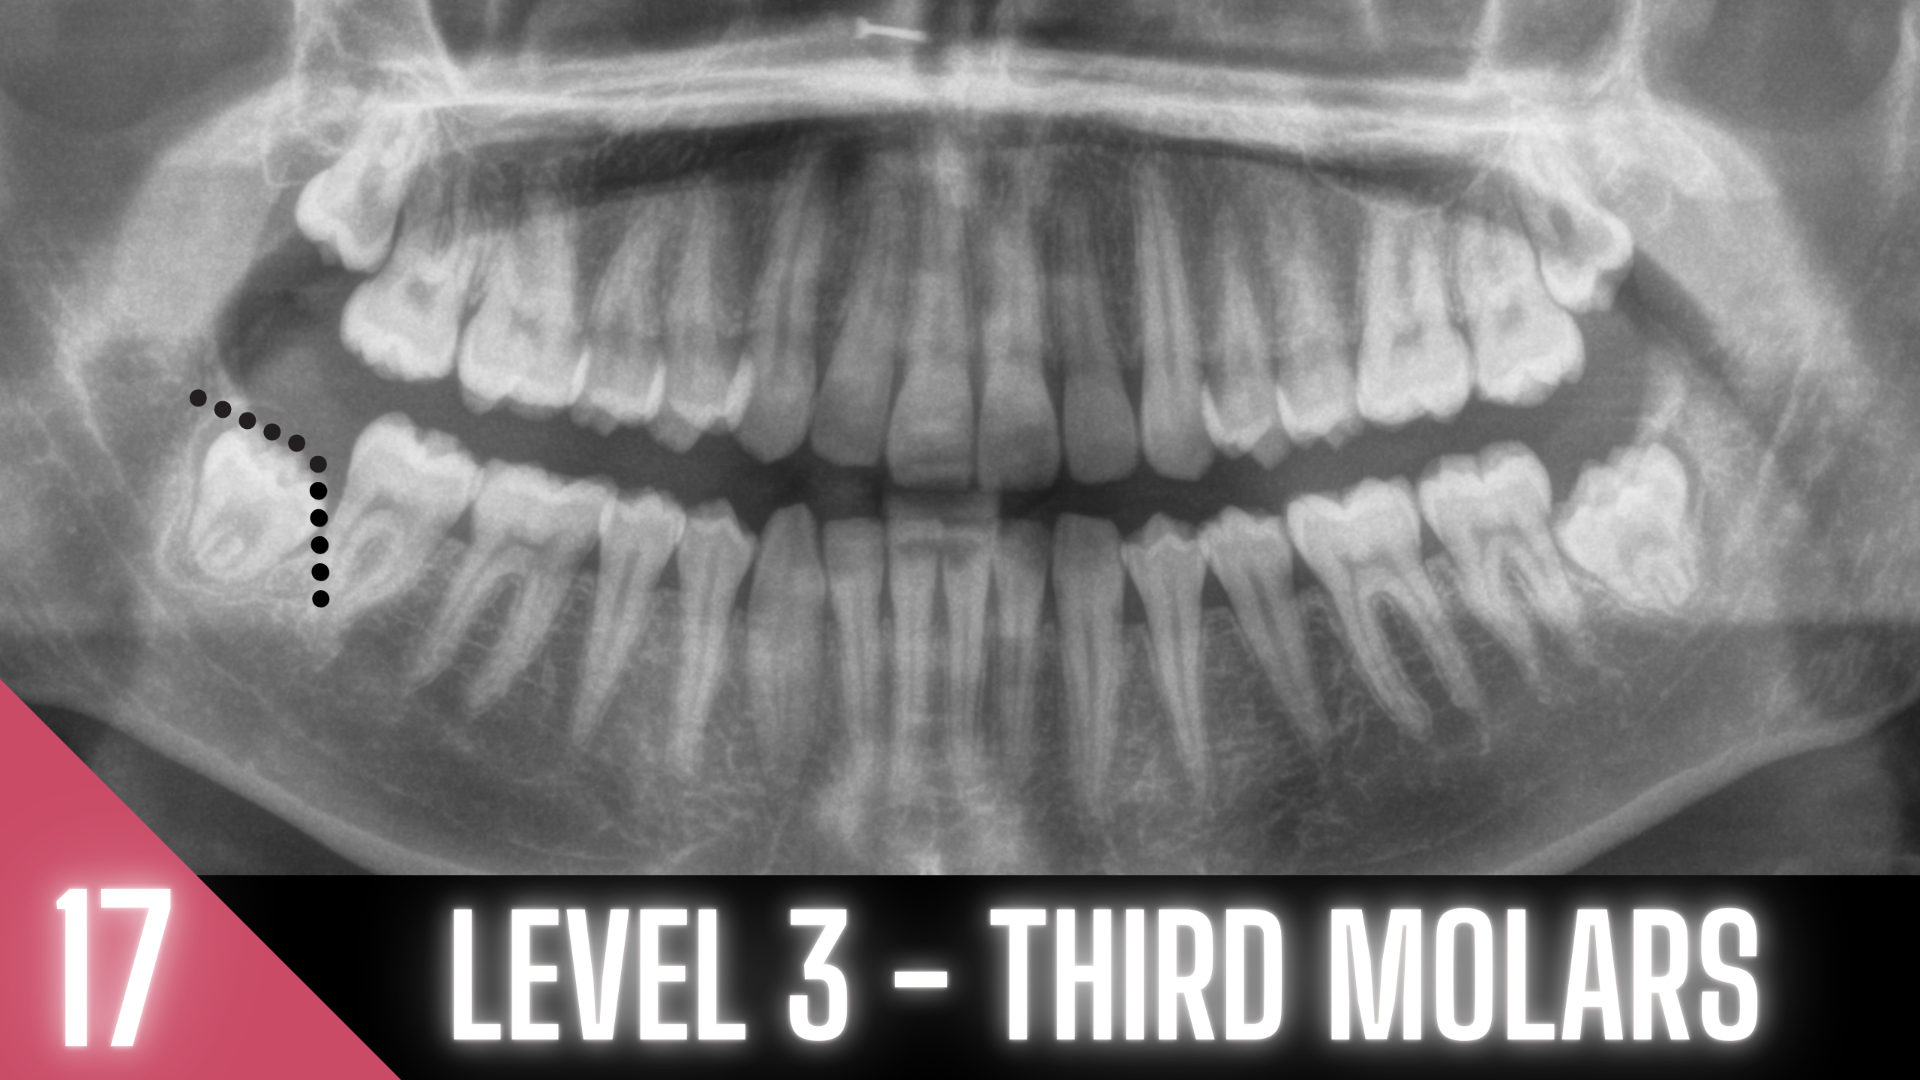

20 MODULES TO MASTER EXODONTIA

Everything you will ever need to know to master exodontia!